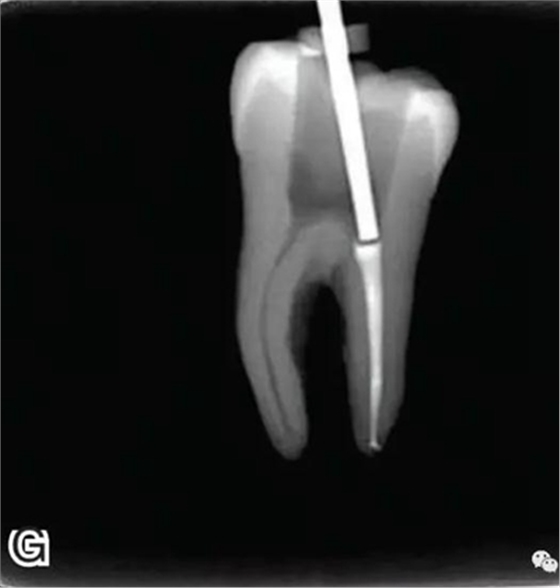

3、試尖

選擇非標(biāo)準(zhǔn)牙膠尖(如0.04、0.06 錐度牙膠尖)作為主尖,型號一般與根管預(yù)備最大號的器械型號一致,能到達(dá)距根尖0.5~1 mm 處,主尖尖段與根管壁緊密接觸。拍試尖X 線片進(jìn)行確認(rèn)(圖3)。

圖3 試尖,A.試主尖 B.拍試尖X片